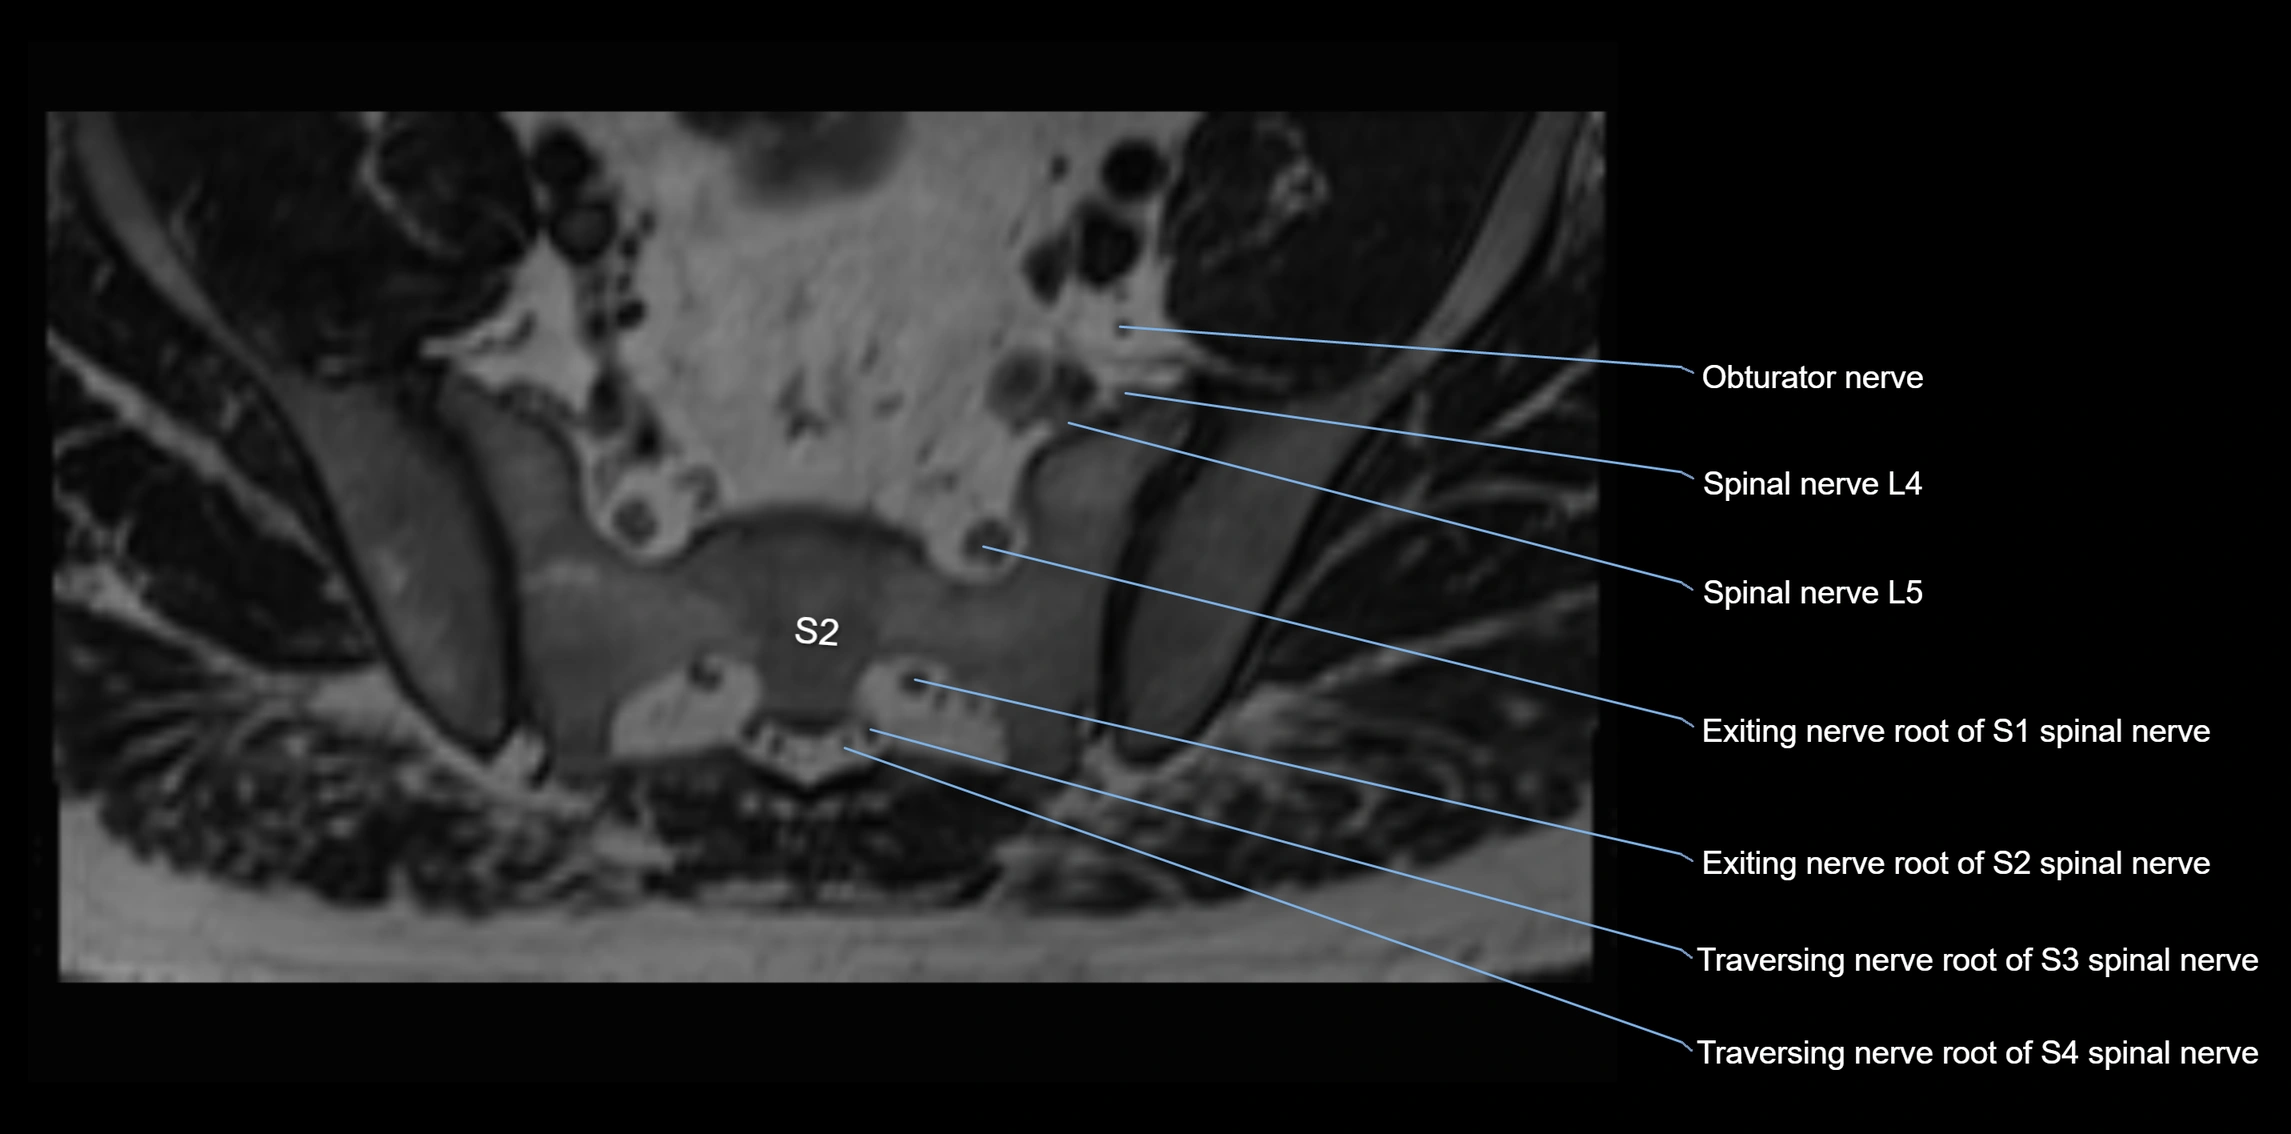

MRI image

image